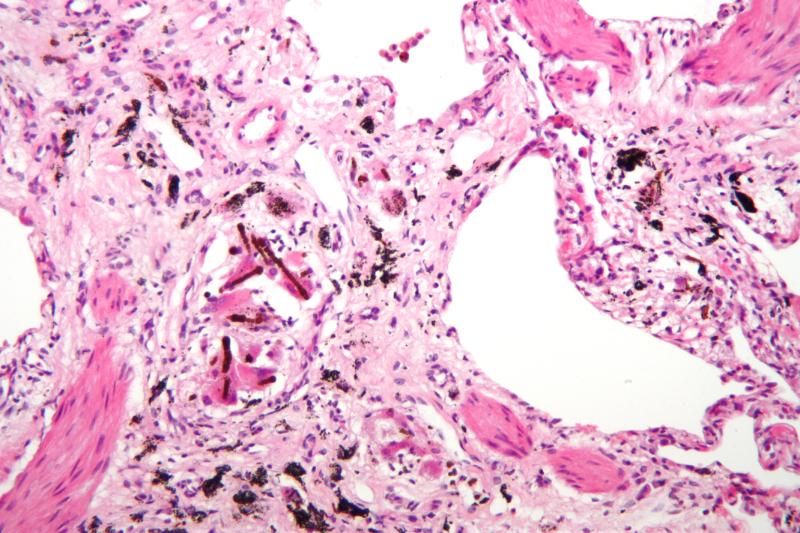

На рентгенограмме при бронхиолите могут наблюдаться признаки гипервоздушности легких (увеличение прозрачности легочных полей), утолщение стенок бронхов (перибронхиальные утолщения) и ателектазы небольших участков легкого. Эти изменения подтверждают поражение мелких бронхиол, но не всегда специфичны.